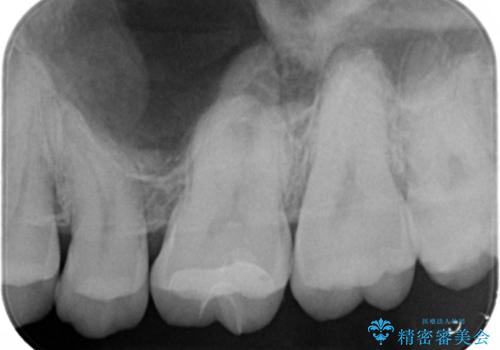

視診だけではわかりづらいですが、レントゲン画像にて昔の詰め物の下に虫歯があることがわかります。